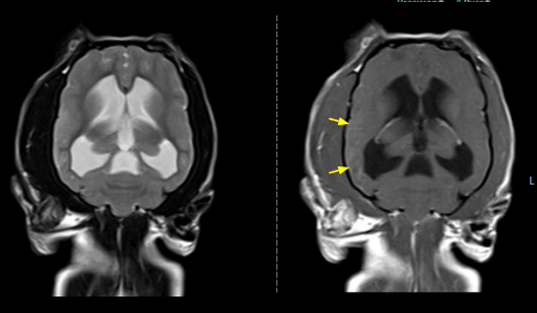

뇌의 질환

염증성 및 감염성 뇌염 (괴상성 뇌수막염, 육아종성 뇌수막염, 각종 감염에 의한 질환 등)

구조적 이상 (후두공 이형성증, 뇌수두증 등)

뇌종양